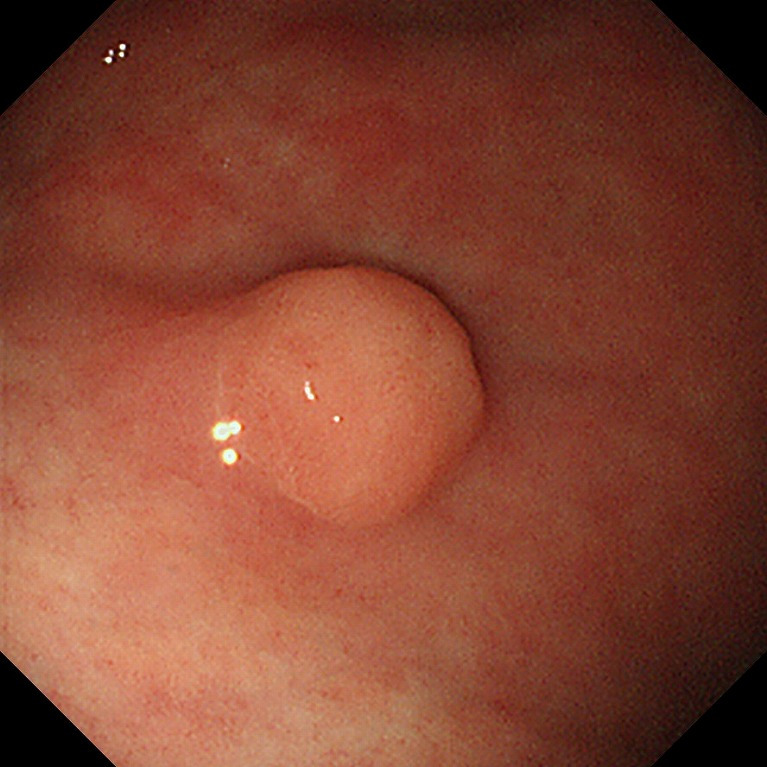

용종 및 선종 감별

위 용종은 대부분 양성이지만, 다음과 같은 경우 조직검사가 필요합니다:

- 크기가 1cm 이상

- 모양이 넓적하거나 불규칙

- 표면이 거칠고 홍반을 동반

- 선종이 의심되는 경우

선종은 훗날 암으로 진행할 수 있기 때문에 내시경 절제술 등을 검토하기 위해 조기 평가가 필요합니다.